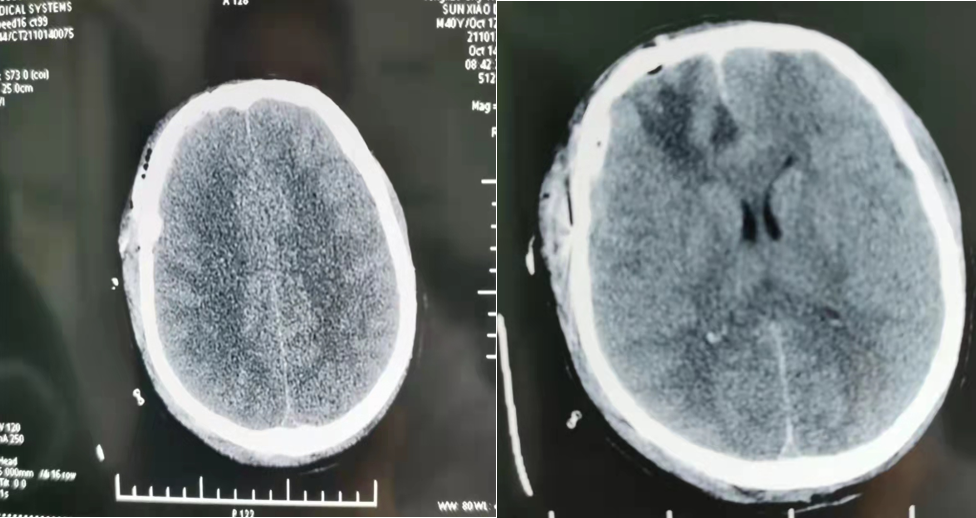

患者男性,43岁,因车祸昏迷脑疝入院,经急诊CT显示颅内硬膜下出血,出血量超过60ml。生死攸关之际,神经外科赵程欣、张永哲、李兵桥三位医生紧急进行术前讨论、分析病情,迅速制定救治方案,在与家属进行了充分沟通后,决定急诊行神经内镜联合显微镜脑内血肿清除术,以最小创伤,争取最大治疗机会。

手术由神经外科主任医师赵程欣与主治医师李兵桥共同完成,术中二人默契配合、紧密协作。因脑部血管和神经组织极为丰富,需要在狭窄的手术区域内辨认和避开正常的血管和神经组织,并清除患者脑内血肿,每一步操作都要求精确无误,因此对术者的医疗技术与心理素质都要求极高。历时两个多小时,手术顺利完成,术后一天复查CT,颅内出血完全清除,患者左侧肢体活动自由,恢复良好,目前已痊愈出院。